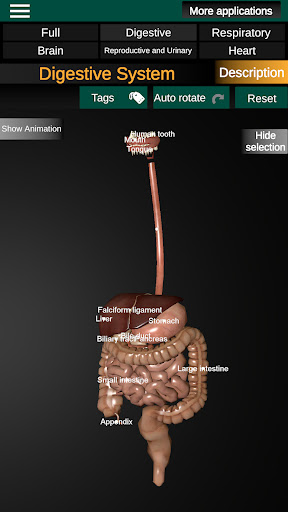

* Sistem pencernaan, termasuk lambung, usus kecil, usus besar, dan animasi sistem ini.